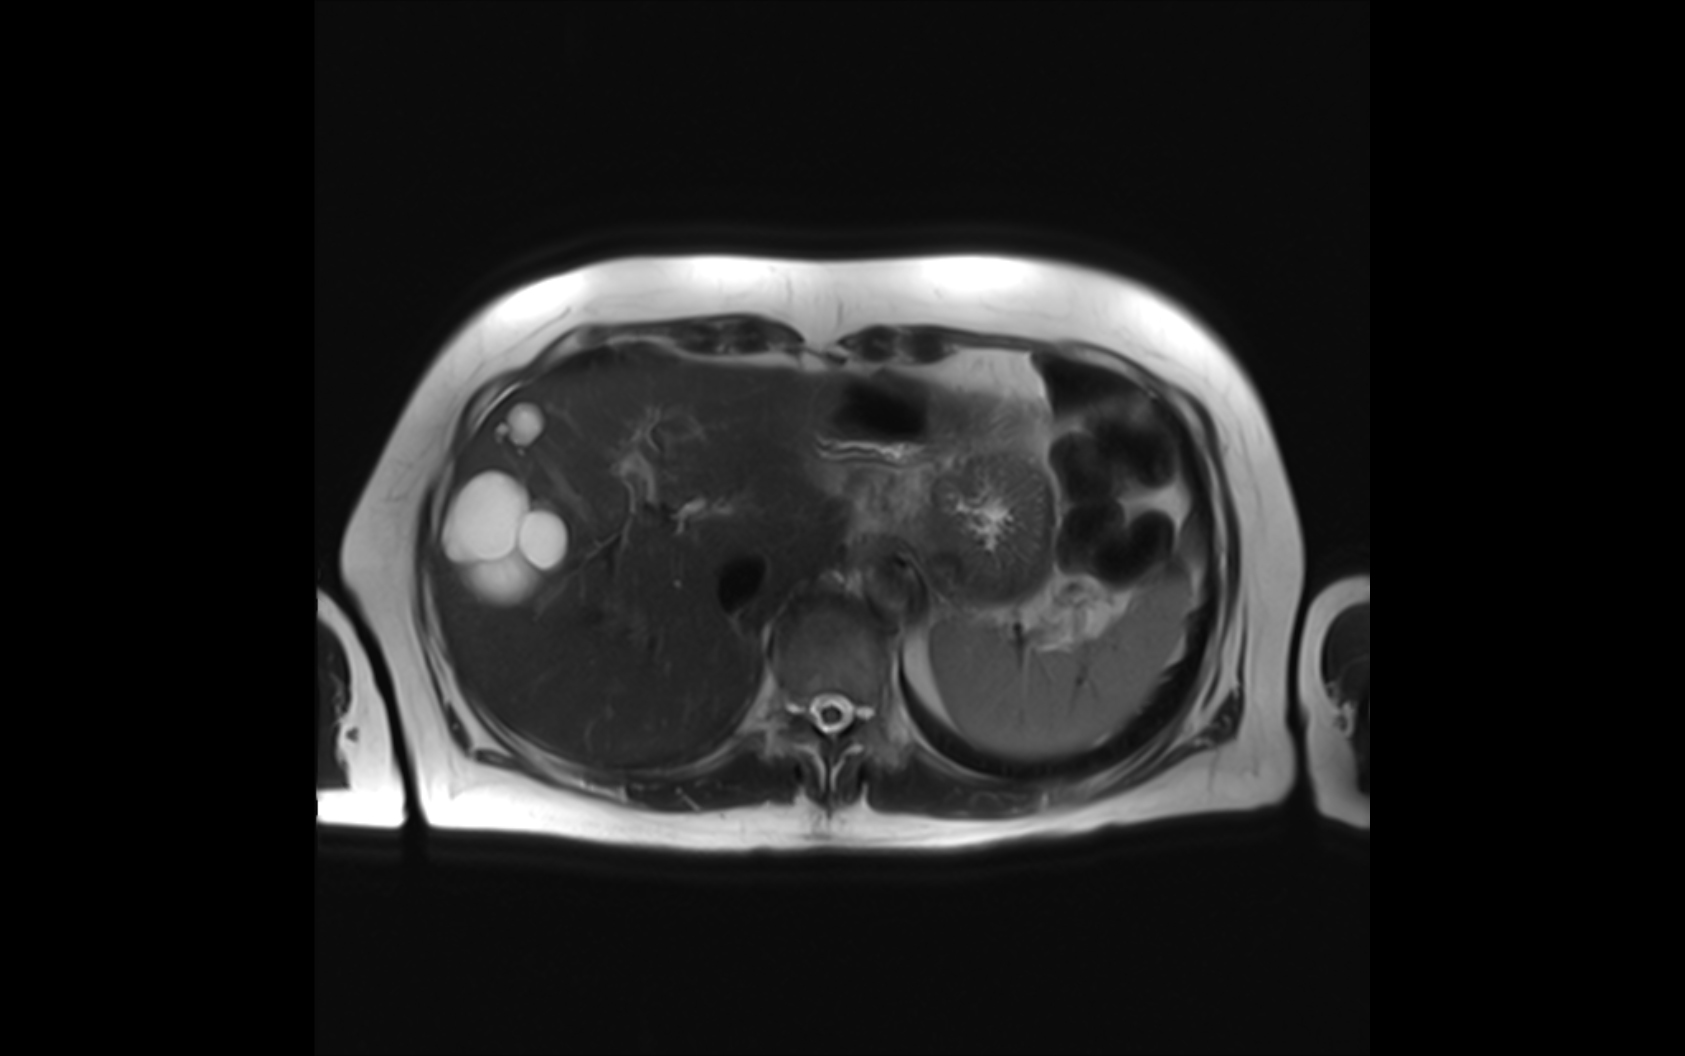

Es gibt einige Gründe, warum Ärztinnen und Ärzte möglichst gute Bilder von der Leber brauchen. Zum Beispiel streuen viele Tumorarten Metastasen in die Leber, die man im Verlauf der Therapie dann im Blick behalten muss. Auch bei der Behandlung alkoholbedingter Leberzirrhosen ist eine gute Bildgebung wichtig.

„Die Röntgentomographie liefert in beiden Fällen Bilder, deren Kontrast nicht immer optimal ist“, sagt Herbert Köstler, Professor für Experimentelle Radiologie am Universitätsklinikum Würzburg. Darum sei im Fall der Leber die MR-Tomographie das Mittel der Wahl. Das Kürzel MR steht für Magnetresonanz – eine Form der medizinischen Bildgebung, die nicht auf Röntgenstrahlen basiert, sondern auf Magnetfeldern.

Ein Nachteil der MR ist es, dass es relativ viel Zeit braucht, um die Bilder aufzunehmen. Will man die Leber gut abbilden, dauert das pro Aufnahme bis zu 20 Sekunden. So lange muss der Patient die Luft anhalten, weil seine Atembewegungen die Bildgebung stören würden. Außerdem können bis zu drei Aufnahmen nötig sein, um ein umfassendes Bild von der Leber zu gewinnen.